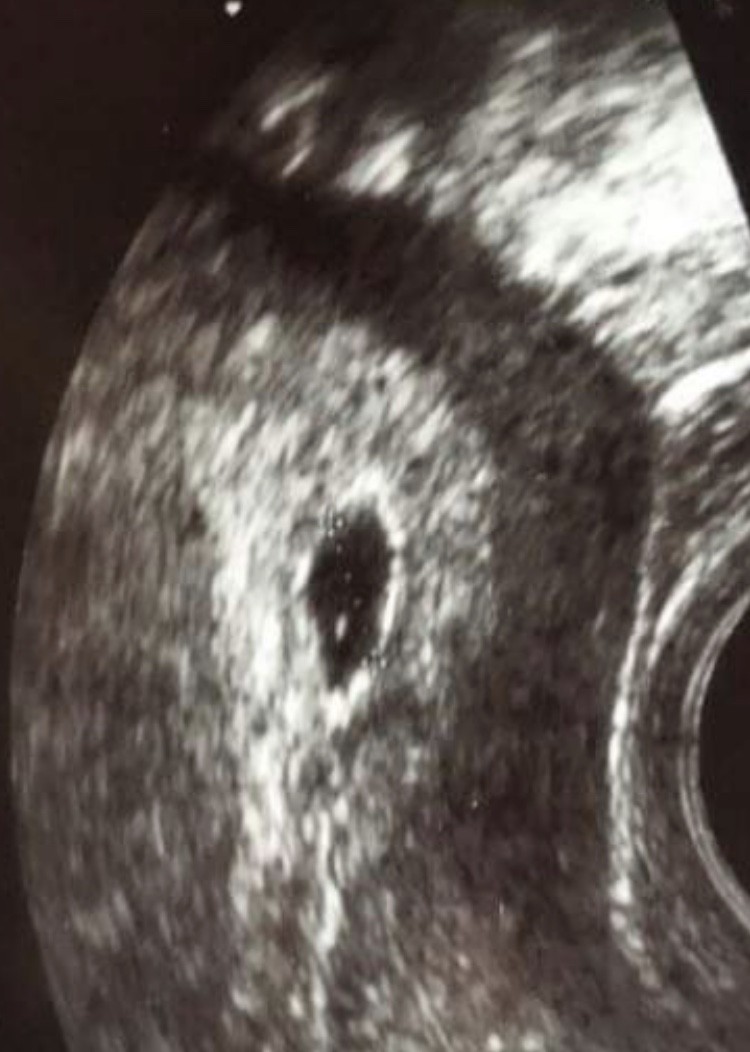

W którym tygodniu jesteś?Witaj, ja też pęcherzyk w kształcie łezki, jeszcze bardziej widocznej niż u Ciebie i wszystko ok. Nie przejmuj się!!!![]()

Zobacz na mój, a teraz 16 tydzieńZobacz załącznik 1300033

Piękny widok. Napawa mnie taka energiaZobacz na mój, a teraz 16 tydzień![]()

Który tydzień miałaś na tym usg?Zobacz na mój, a teraz 16 tydzień![]()

5t5dKtóry tydzień miałaś na tym usg?